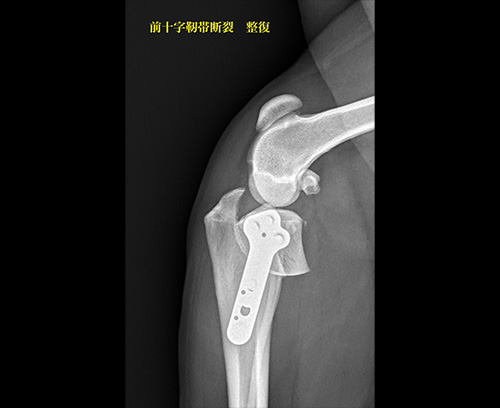

前十字靭帯断裂

前十字靭帯断裂(TPLO)

十字靭帯断裂(TPLO)